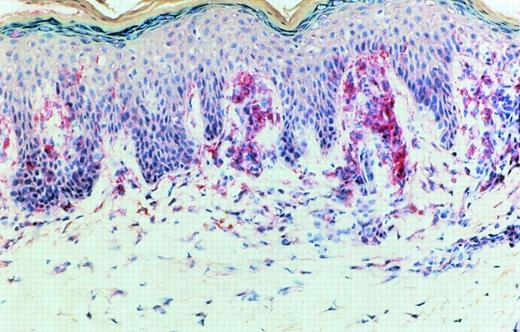

Immunoreactivity for IL-15 was detected in epidermal cells, especially in the basal layer of the epidermis, in cells with a dendritic morphology in the dermis and in mononuclear cells. This immunoreactivity could be blocked by exogenous recombinant IL-15. In early CTCL lesions (patches) (n = 5), immunoreactivity was strongest in the junction zone between epidermis and dermis where the lymphocytic infiltrates show their highest densities (Fig 7). In advanced lesions (plaques) (n = 5), immunoreactivity was also detected in deeper parts of the dermis in areas heavily infiltrated by mononuclear cells (Fig 8).

Detection of IL-15 in early CTCL lesion (patch stage) by an IL-15 antibody. The binding of the specific antibody to IL-15 was detected by an alkaline phosphatase (AP) coupled second antibody directed against the Fc region of the IL-15 antibody. Binding of the IL-15 antibody after APAAP staining was strongest in the junction zone between epidermis and dermis where CTCL cells show their highest densities. The specificity of the binding of the IL-15 antibody was tested by a competition experiment with recombinant IL-15 (not shown).

Our immunohistological investigations detected IL-15 immunoreactivity restricted to the junction zone between epidermis and dermis in early lesions of MF (Fig 7). In this area keratinocytes, dermal dendritic cells, or lymphocytes could produce this cytokine. Because the area of IL-15 production includes the area where CTCL cells preferentially home, we propose that IL-15 is a paracrine/autocrine growth or viability factor and/or a chemotactic factor in early CTCL lesions.